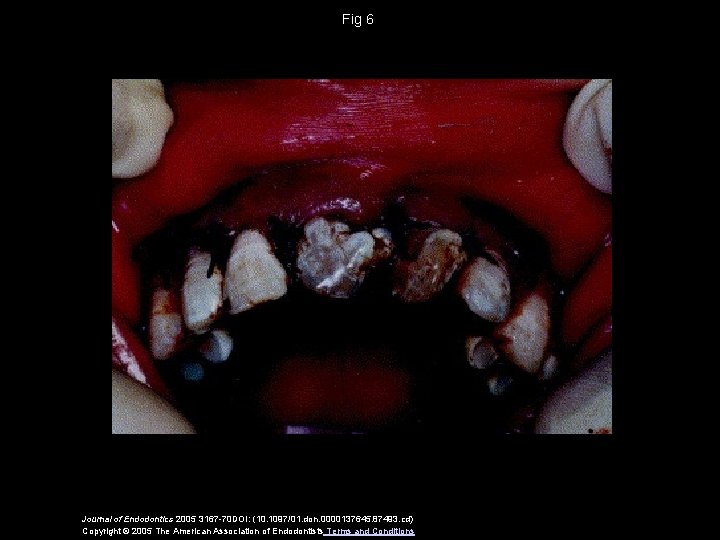

Fig 6 Journal of Endodontics 2005 3167 -70 DOI: (10. 1097/01. don. 0000137645. 87493. cd) Copyright © 2005 The American Association of Endodontists Terms and Conditions